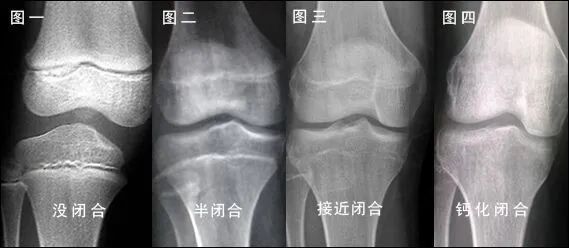

有呀。一般小朋友要長(zhǎng)高,骨骼生長(zhǎng)功不可沒(méi),長(zhǎng)骨的兩端存在著非常特殊的區(qū)域——骨骺和生長(zhǎng)板,骨骼變長(zhǎng)就是通過(guò)這一區(qū)域的生長(zhǎng)來(lái)實(shí)現(xiàn)的。同時(shí),隨著年齡的增長(zhǎng),骨骺的生長(zhǎng)逐漸緩慢,生長(zhǎng)板逐漸變薄,最終完全與骨骺融合后便不會(huì)生長(zhǎng),人也就不能繼續(xù)長(zhǎng)高。因此,我可以用來(lái)判斷骨的發(fā)育程度,預(yù)測(cè)兒童的成年后身高,此外還能為某些內(nèi)分泌疾病、營(yíng)養(yǎng)障礙的診斷提供參考。